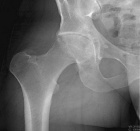

28 year old male with progressive right hip pain for one year

Zoom image: Radiological image Radiological image.